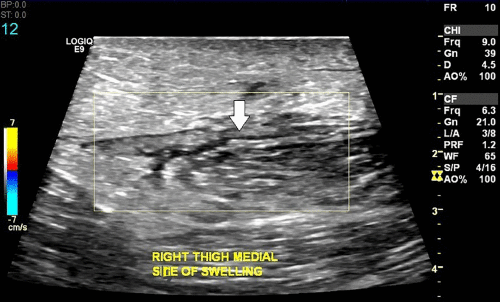

Filarial Dance Sign Ultrasound

Filarial Dance Radiology Case Radiopaedia Org

Filarial Dance Sign On Scrotal Ultrasound W Bancrofti This Grepmed

Scrotal Filariasis The Importance Of Filarial Dance Sign In Scrotal Ultrasound

Scrotal Ultrasound Shows The Characteristic Filarial Grepmed